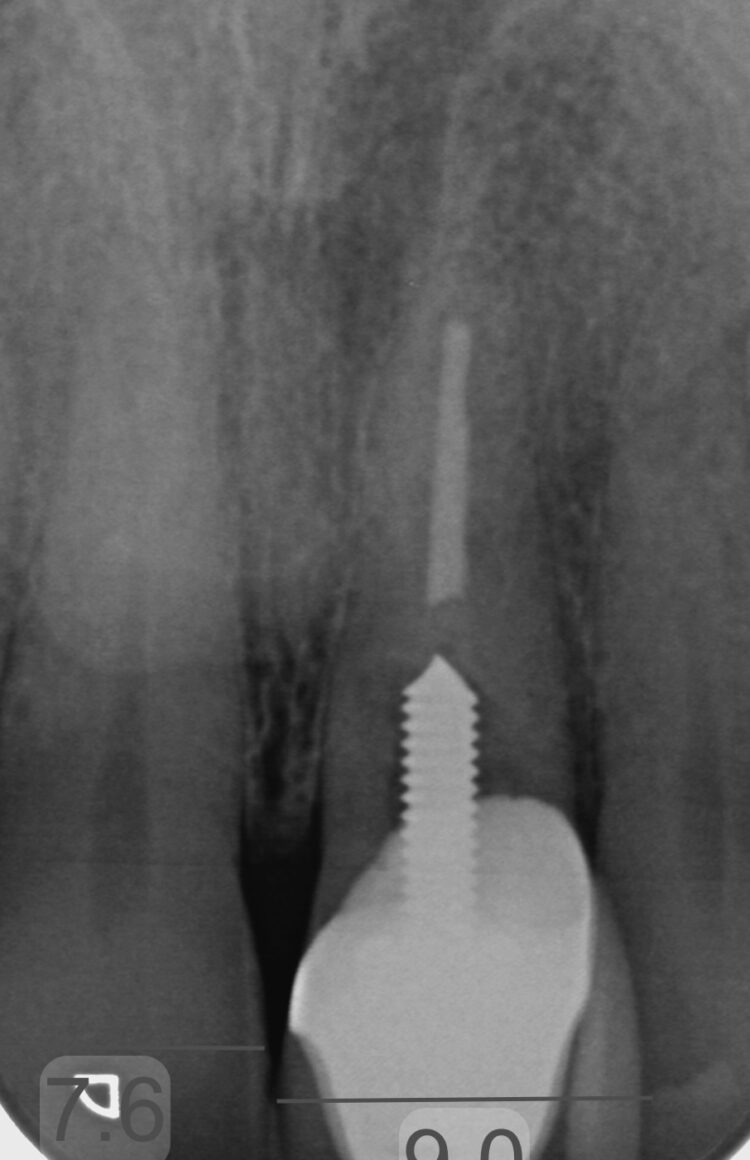

Following the clinical & radiographic examinations, it was identified that the UL1 was restored with a post-retained crown and suffering with internal resorption. It also highlighted that the alveolar ridge was extremely narrow.

The treating orthodontist advised that the UL1 should be removed prior to orthodontic treatment and the replacement options were discussed with the patient who preferred an implant retained restoration. The concern remained that whilst upper and lower orthodontics were being carried out, there would be vast hard & soft tissue resorption rendering implant treatment to require complex, staged procedures in due course.